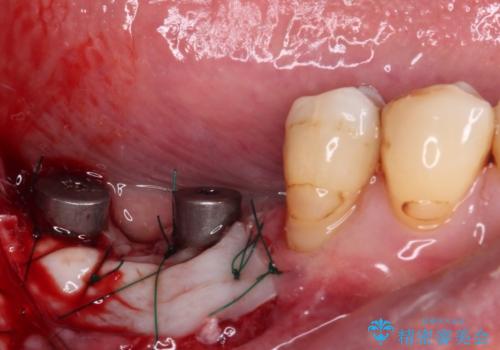

- 60歳を越え、黄ばんだ前歯をセラミッククラウンできれいな口元にしたいとのことで来院された患者様です。

診察したところ、前歯は反対咬合であり、その影響で抜歯が必要な奥歯があることが分かりました。

抜歯が必要な奥歯は、インプラント並びにブリッジにより補綴を行い、上下前歯は反対咬合を改善させるように補綴治療を行うこととしました。

健全な歯を削ってセラミッククラウンに置き換えることは、本来避けるべき治療と考えますが、今回は①患者様が60歳を越えていること、②要改善の咬合により抜歯が必要な奥歯があること、③反対咬合の前歯改善の手段としてセラミック治療が選択肢にあることなどから、全顎的なセラミック治療を行うこととしました。